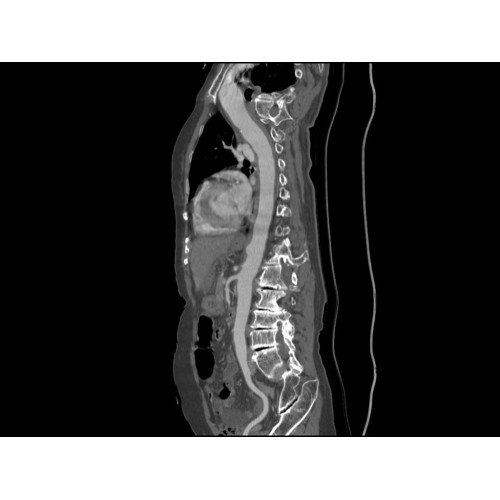

Позволяет проводить комплексные исследования всех анатомических зон, включая нейровизуализацию, ангиографию, исследования органов грудной и брюшной полости. Особенно эффективен для раннего выявления онкологических заболеваний.